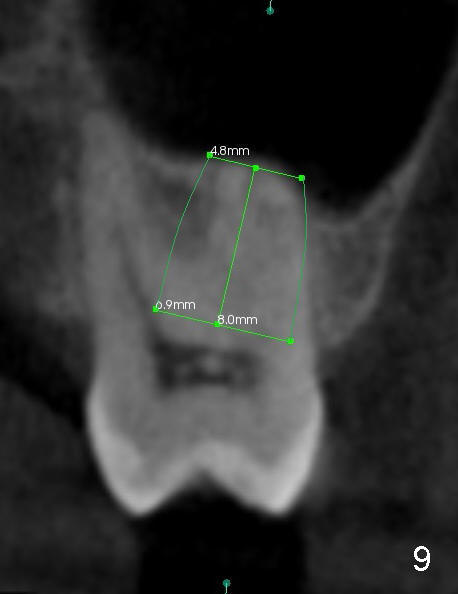

The 2nd best site for implantation in this case is the buccal socket, which is large with thicker buccal bone (Fig.9). Although the apex of the implant is buccal, the base of it can be leaned palatal using bone manipulation.